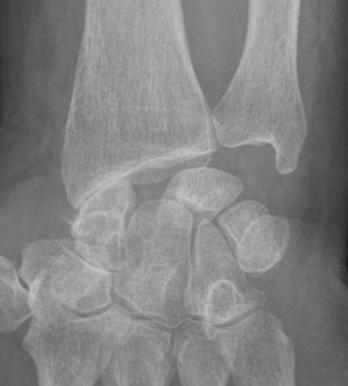

SLAC wrist : Noter le diastasis entre le scaphoïde et le lunatum, les remaniements dégénératifs radio-scaphoïdien, et scapho-trapézo-trapézoïdien. Respect de l’interligne radio-lunaire